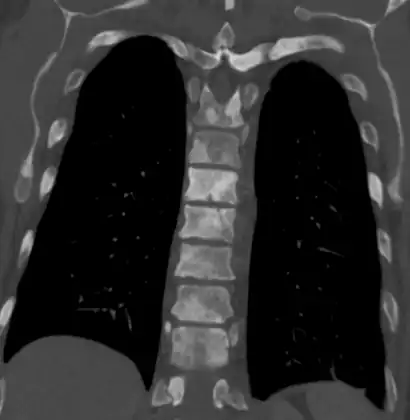

-

Sclerosis of the bones of the thoracic spine due to prostate cancer metastases (CT image) -